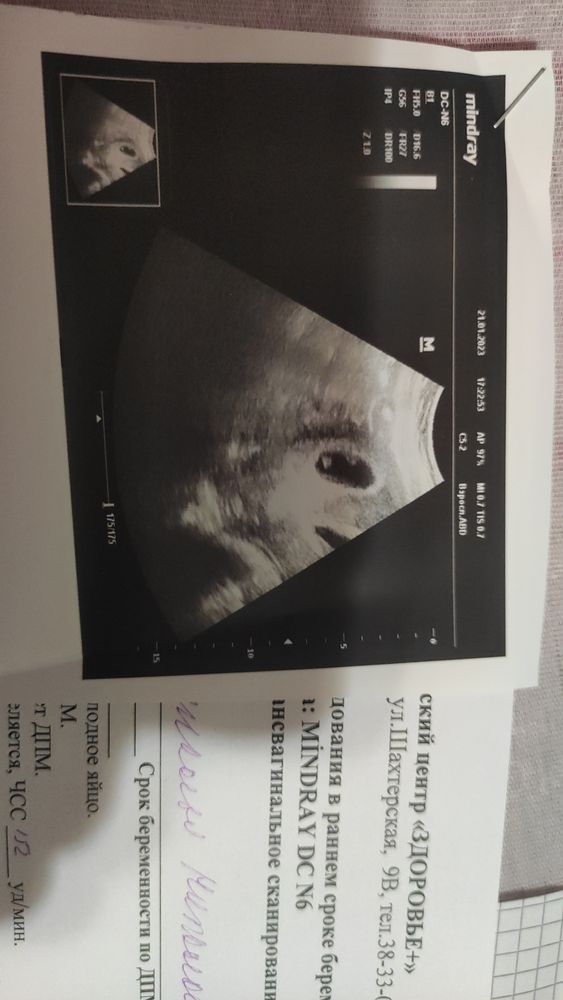

Девочки здравствуйте. Посмотрите пожалуйста. Скинула фото УЗИ знакомой что работает в роддоме, она меня заинтриговала. Говорит похоже на двоих. Я была бы только рада. Собираюсь в начале месяца домой, к своему лечащему врачу, который отправлял на эко дважды. Брать справку что отправить на работу, т.к беременные не могут ездить на вахту. Может по УЗИ видно двоих.... Спасибо🙏💕

Очень похоже на однояйцовых близнецов, хотя может и жм и эмбрион. Узи конечно надо повторить через недельку) Пусть будут близнецы)

Мне тоже кажется, что два малышика, дай бог. Я сама из двойняшек, и мечтаю о двойне